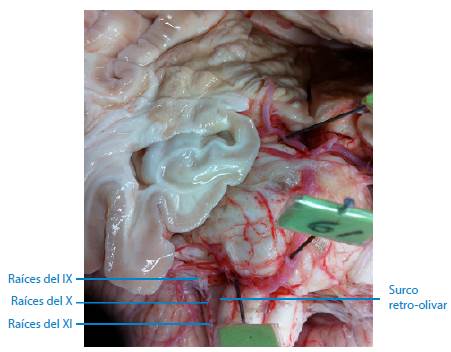

De los 67 troncos encefálicos estudiados, se encontró que en ninguno de ellos las raíces nerviosas de los nervios glosofaríngeo, vago y accesorio hacían su aparición como origen aparente en el surco retro-olivar, tal como se describe en la literatura consultada. Se observó que, en el 100% de las piezas neuroanatómicas estudiadas, el origen aparente de estos tres nervios craneales forma una línea continua de raicillas que se localiza entre 2mm a 3mm por detrás del surco retro-olivar, en sus lados derecho e izquierdo, concretamente en las áreas retro-olivares, tal como se puede apreciar en las Figuras 1, 2, 3 y 4. Además, no se evidencia ningún surco en aquel sitio por donde emergen las raicillas de estos nervios craneales.

Surco retro-olivar donde las raíces nerviosas emergen por detrás del surco y no a través de él.

Figura 1: Surco retro-olivar donde las raíces nerviosas emergen por detrás del surco y no a través de él.

Fuente: Elaboración propia.

Línea continua de raíces nerviosas que emergen por detrás del surco retro-olivar.

Figura 3: Línea continua de raíces nerviosas que emergen por detrás del surco retro-olivar.

Múltiples autores indican que el origen aparente de los nervios glosofaríngeo, vago y accesorio se encuentra en el surco retro-olivar 5,6,18,19 o surco post-olivar 7,9,20. Sin embargo, una inspección más detallada en las muestras estudiadas sobre dicho sitio de origen revela que tal descripción no es cierta y carece de precisión, por lo que se sugiere hacer más estudios en otros lugares geográficos y con una muestra mayor, esto con el fin de precisar dicho sitio de emergencia o revaluar este concepto. En los 67 troncos encefálicos utilizados para este trabajo, se encontró que en ninguno de ellos las raicillas nerviosas de estos nervios craneales emergen por los surcos retro-olivares. En el 100% de las piezas neuroanatómicas analizadas, se evidenció y registró fotográficamente que las raicillas nerviosas hacen su aparición entre 2mm a 3mm por detrás del surco retro-olivar en sus lados derecho e izquierdo, concretamente en las áreas retro-olivares; además, contrario a lo que se registra en la literatura, no se observó la presencia de ningún surco en aquel sitio por donde emergen las raicillas nerviosas.

Los nervios craneales glosofaríngeo, vago y accesorio no tienen su origen aparente en el surco retro-olivar, como tradicionalmente se describe en los textos y artículos referenciados. El verdadero origen aparente de estos nervios ocurre entre 2mm a 3mm por detrás del surco retro-olivar, lugar donde se aprecia una línea continua de raicillas nerviosas que se hacen visibles en ambos lados de la médula oblongada, en específico en las áreas retro-olivares. Tampoco se encontró evidencia de ningún surco en el sitio donde supuestamente emergen las raicillas de estos nervios craneales, distinto a lo que se describe en la literatura.